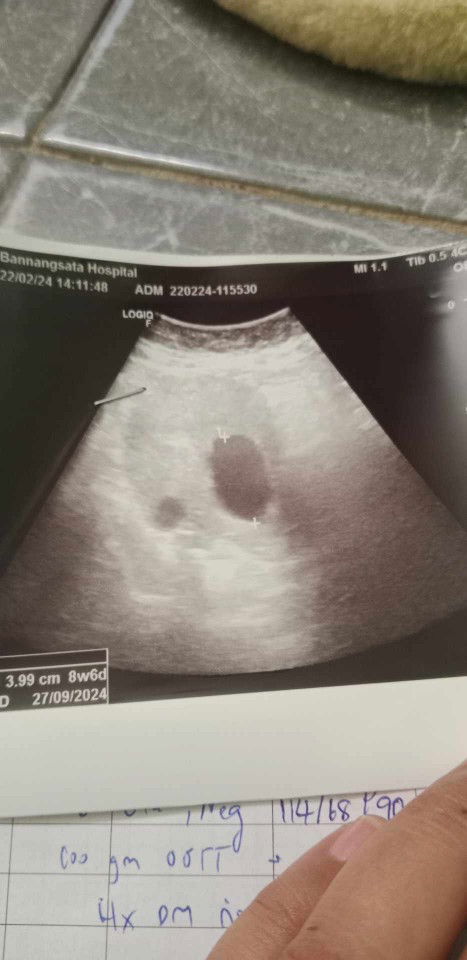

11w3dเมื่อวานไปโรงบาลซาวด์ หมอบอกไม่เห็นน้อง หมอบอกอาจจะท้องลม หรือไม่ก็ท้องยังอ่อนเลยไม่เห็นแม่เครียดมากค่ะ ร้องไห้ วันนี้จะไปซาวด์คลีนิกดูค่ะ แม่ๆๆคนไหนมีประสบการณ์แบบนี้บ้างค่ะ ขอความคิดเห็นหน่อยค่ะ เพื่อความสบายใจของแม่